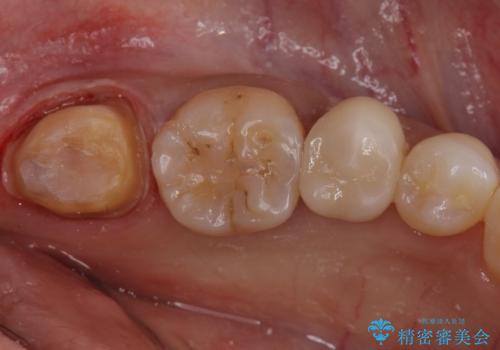

今回の場合、虫歯の大きさが大きく本来であれば歯茎に対しても治療をすることが検討されケースですが、ご希望されなかったため被せ物のみでの治療となりました。